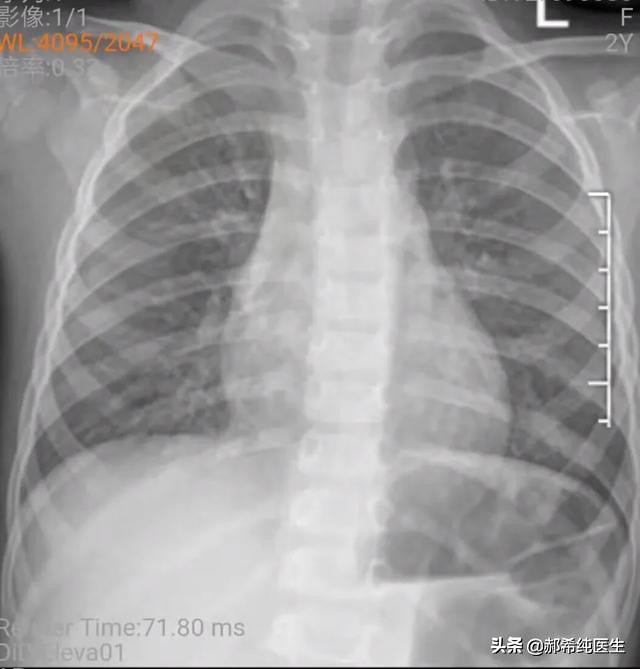

第三天的时候,白天开始出现了一次发热,体温38.5,妈妈还好,可是外婆忍不住了,说发热都3天了,怎么可以不吃药,还说她女儿是不是亲妈啊,自己才是亲外婆[允悲],结果愣是跑到医院去了,你们也知道的,到了医院,当地医生,一般都是一个套路,抽血加拍片。

好在小朋友妈妈第一时间把片子传我了,我说,目前来看,病毒性原因仍然要首先考虑,尤其是这个年龄段的孩子,肺部感染首先需要考虑病毒性的,当然我说的病毒,不一定是流感病毒啦。